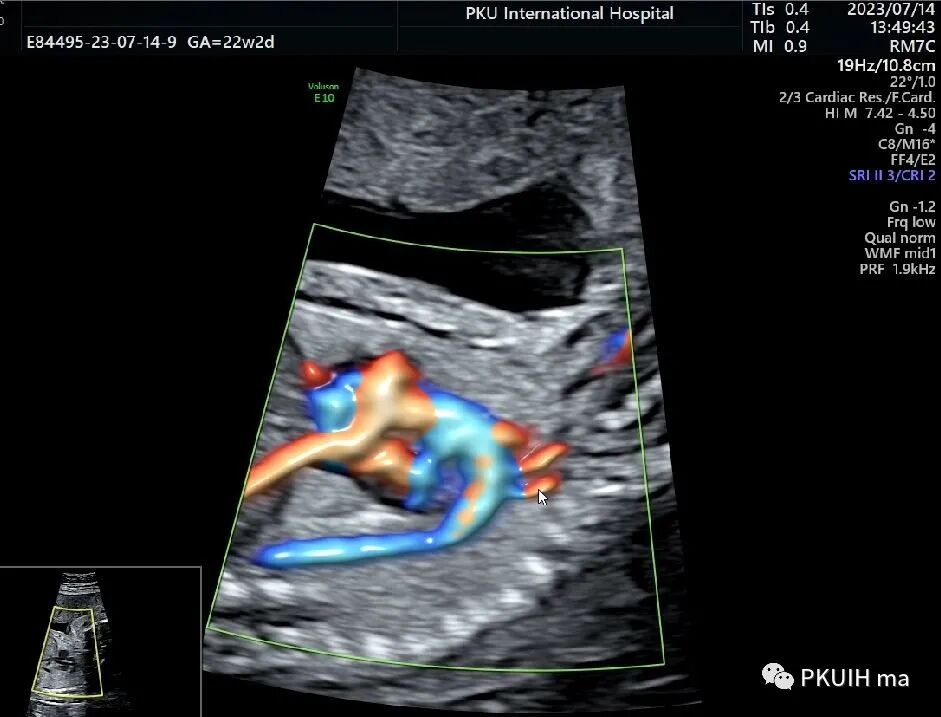

下面几张图是正常的主动脉弓长轴二维及血流图像